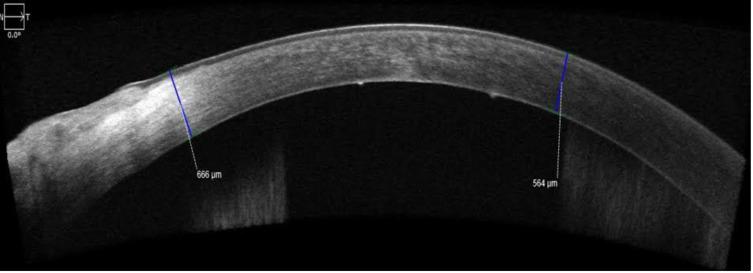

Descemet's membrane detachment (DMD) is a complication fundamentally associated with cataract surgery, the subclinical presentation being higher than expected. There are many varied treatments, from simple observation to penetrating keratoplasty. We present a case report of a 78-year-old male patient, without comorbidities, who underwent cataract surgery with phacoemulsification plus intraocular lens implantation in the capsular bag of the left eye. During the intraoperative procedure, he presented a DMD (height of 350 um and length of 3 mm in Zone 1 according to the HELP algorithm), managed with adaptive viscoelastic under the soft-shell technique in the same operative act, injection of iso-expansile SF6 (20%) intracameral plus postural positioning for 2 hours carried out 48 hours after surgery plus intensive topical treatment with hypertonic sodium chloride and steroidal anti-inflammatory drugs. At 72 hours after the operation of the application of the gas bubble, he presented with a transparent cornea and a best-corrected visual acuity of 20/80, which finally for his ophthalmological control at 8 weeks presented definitive resolution of the case in the AS-OCT and with a BCVA of 20/30.

Descemet膜脱离(DMD)是一种与白内障手术密切相关的并发症,其亚临床表现高于预期。治疗方法多种多样,从简单观察到穿透性角膜移植术。我们报告一例78岁男性患者,无合并症,左眼行囊袋内白内障超声乳化吸除联合人工晶状体植入术。术中,他出现了DMD(根据HELP算法,在1区高度为350μm,长度为3mm),在同一手术中采用软壳技术下的自适应粘弹剂处理,术后48小时前房内注射等膨胀性SF6(20%)并体位保持2小时,同时联合高渗氯化钠和甾体类抗炎药进行强化局部治疗。在应用气泡手术后72小时,他的角膜透明,最佳矫正视力为20/80,最终在8周的眼科检查中,AS-OCT显示该病例得到明确解决,最佳矫正视力为20/30。